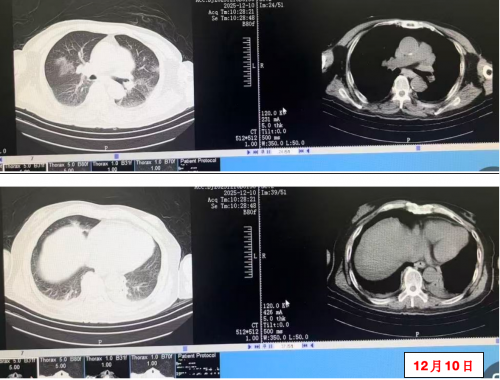

12月10日 复查CRP21mg/L,复查胸部CT较前好转,请普通病房会诊后转至普通病房继续治疗。

12月10日胸部CT: